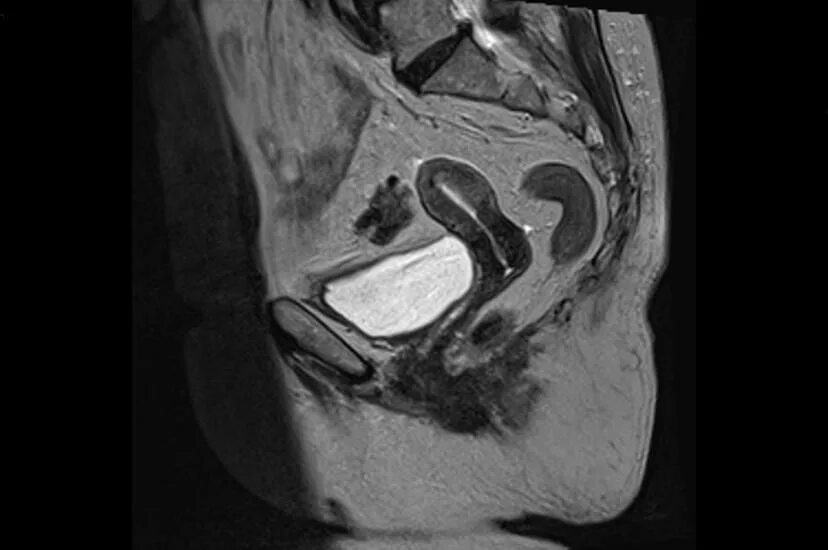

Можно ли сделать мрт малого таза